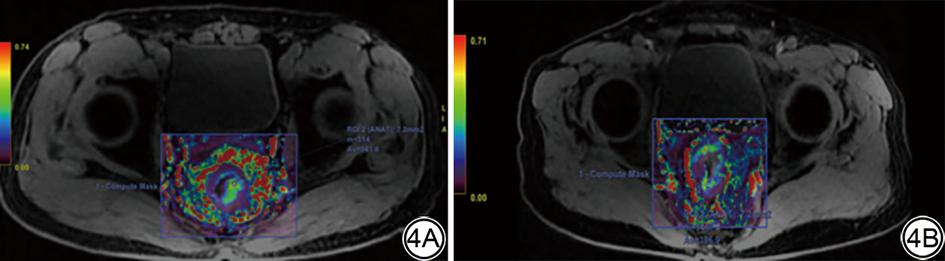

将轴位DCE-MRI、T2WI及ADC原始图像(DICOM)导入3D Slicer 4.11.0软件(https://github.com/Slicer/Slicer/releases)中,两位放射科医师(分别为具有5年工作经验的主治医师与15年以上工作经验的副主任医师)分别手动沿着肿瘤最大截面边缘勾画肿瘤最大层面感兴趣区(region of interest, ROI):(1)避开坏死、出血及气体等部分;(2)勾画区域不超过肿瘤边界;(3)选取动态增强最明显期像进行勾画,T2WI及ADC图勾画时,需参照增强序列进行匹配。详见图1

图1  ROI 勾画示意图。女,68 岁,病理诊断为直肠中分化腺癌,图片红色区域分别为轴位DCE-T1WI 图ROI 区域(1A),匹配的T2WI 图ROI 区域(1B)及ADC图ROI 区域(1C)的示意图。ROI:感兴趣区;DCE:动态对比增强;ADC:表观弥散系数。

Fig. 1  ROI delineation diagram. A 68-year-old female patient with rectal moderately differentiated adenocarcinoma, the red areas in the images represent the ROI regions of the axial DCE-T1WI (1A), the corresponding T2WI (1B), and ADC (1C) images. ROI: region of interest; DCE: dynamic contrast-enhanced; ADC: apparent diffusion coefficient.